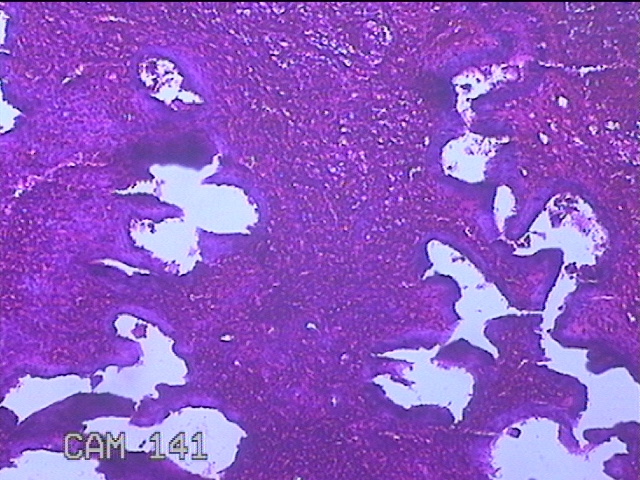

宫腔内容物

性别

女

年龄

40岁

临床诊断

异常子宫出血 子宫内膜息肉

一般病史

同房后出血3月。

标本名称

大体所见

灰白粉红色不规则碎组织3.5x3x0.8cm一堆。

图1